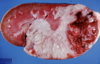

Part 1 - DESCRIBE the change(s) shown.

Part 2 -Provide a MORPHOLOGIC DIAGNOSIS.

Part 3 - Name the type of inflammatory response you would expect to see associated with this lesion in this species.

A

1. The normal architecture of the central portion of the lymph node is disrupted and replaced by aggregates of pale tan, firm material that is forming lamellations

2. Moderate, regionally extensive/focal, chronic, caseous lymphadenitis

3. Granulomatous